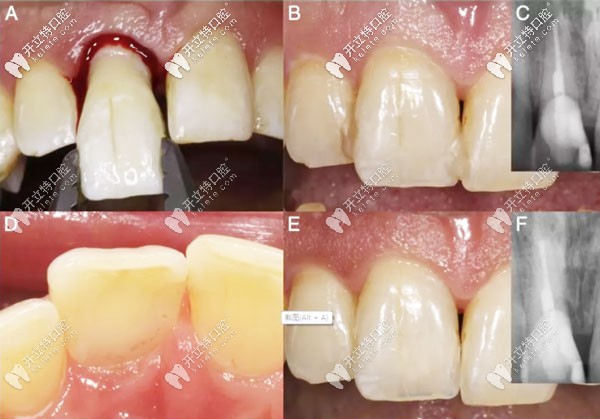

意向性再植術(shù)過(guò)程圖解

意向性牙再植術(shù)的預(yù)后示意圖